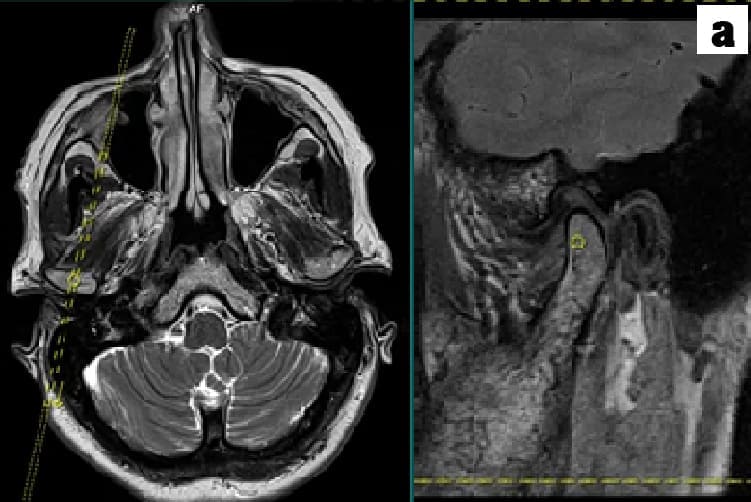

a. Migraines and TMJ disorders are diagnosed primarily through a detailed medical history and physical examination

b. For migraines, criteria from the International Classification of Headache Disorders are used, while TMJ disorders involve assessing jaw movement, tenderness and potential imaging like X-rays, MRIs or OPG to evaluate joint structure.

a. The TMJ is a sliding "ball and socket"  Joint located in front of each ear , where the upper & lower jaws meet. Its the joint that works when the mouth is opened and closed together.

b. The ball-shaped condyle on the lower jaw glides along the socket in the skull base when you open your mouth, and slides back when you close your mouth.

c. Inside the TM joint is a disc that provides a cushion between the upper and lower jaw when it is opened and closed.

d. Connective tissue (Retrodiscal tissue) containing blood vessels and nerves attach the disc to the joint.